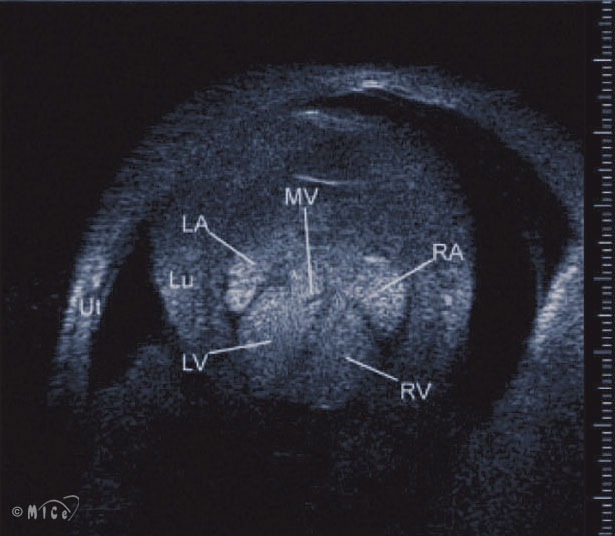

UBM cardiac imaging of the mouse embryo in utero. The embryonic heart at E13.5. LA: left atrium; LV: left ventricle; RA: right atrium; RV: right ventricle; Lu: lung; MV: mitral valve; Ut: Uterus.